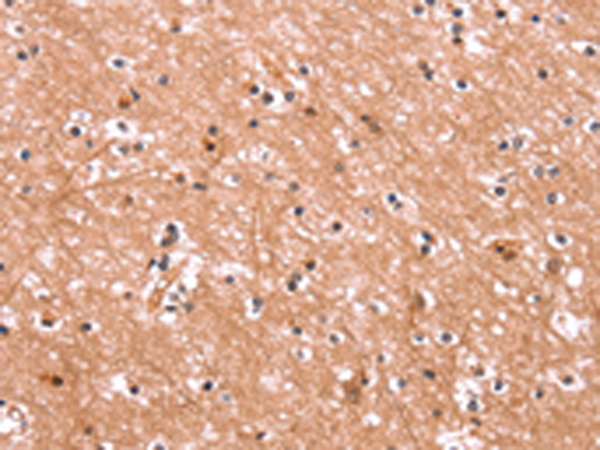

The image is immunohistochemistry of paraffin-embedded Human brain tissue using P11737(ENPP4 Antibody) at dilution 1/15. (Original magnification: ×200) |